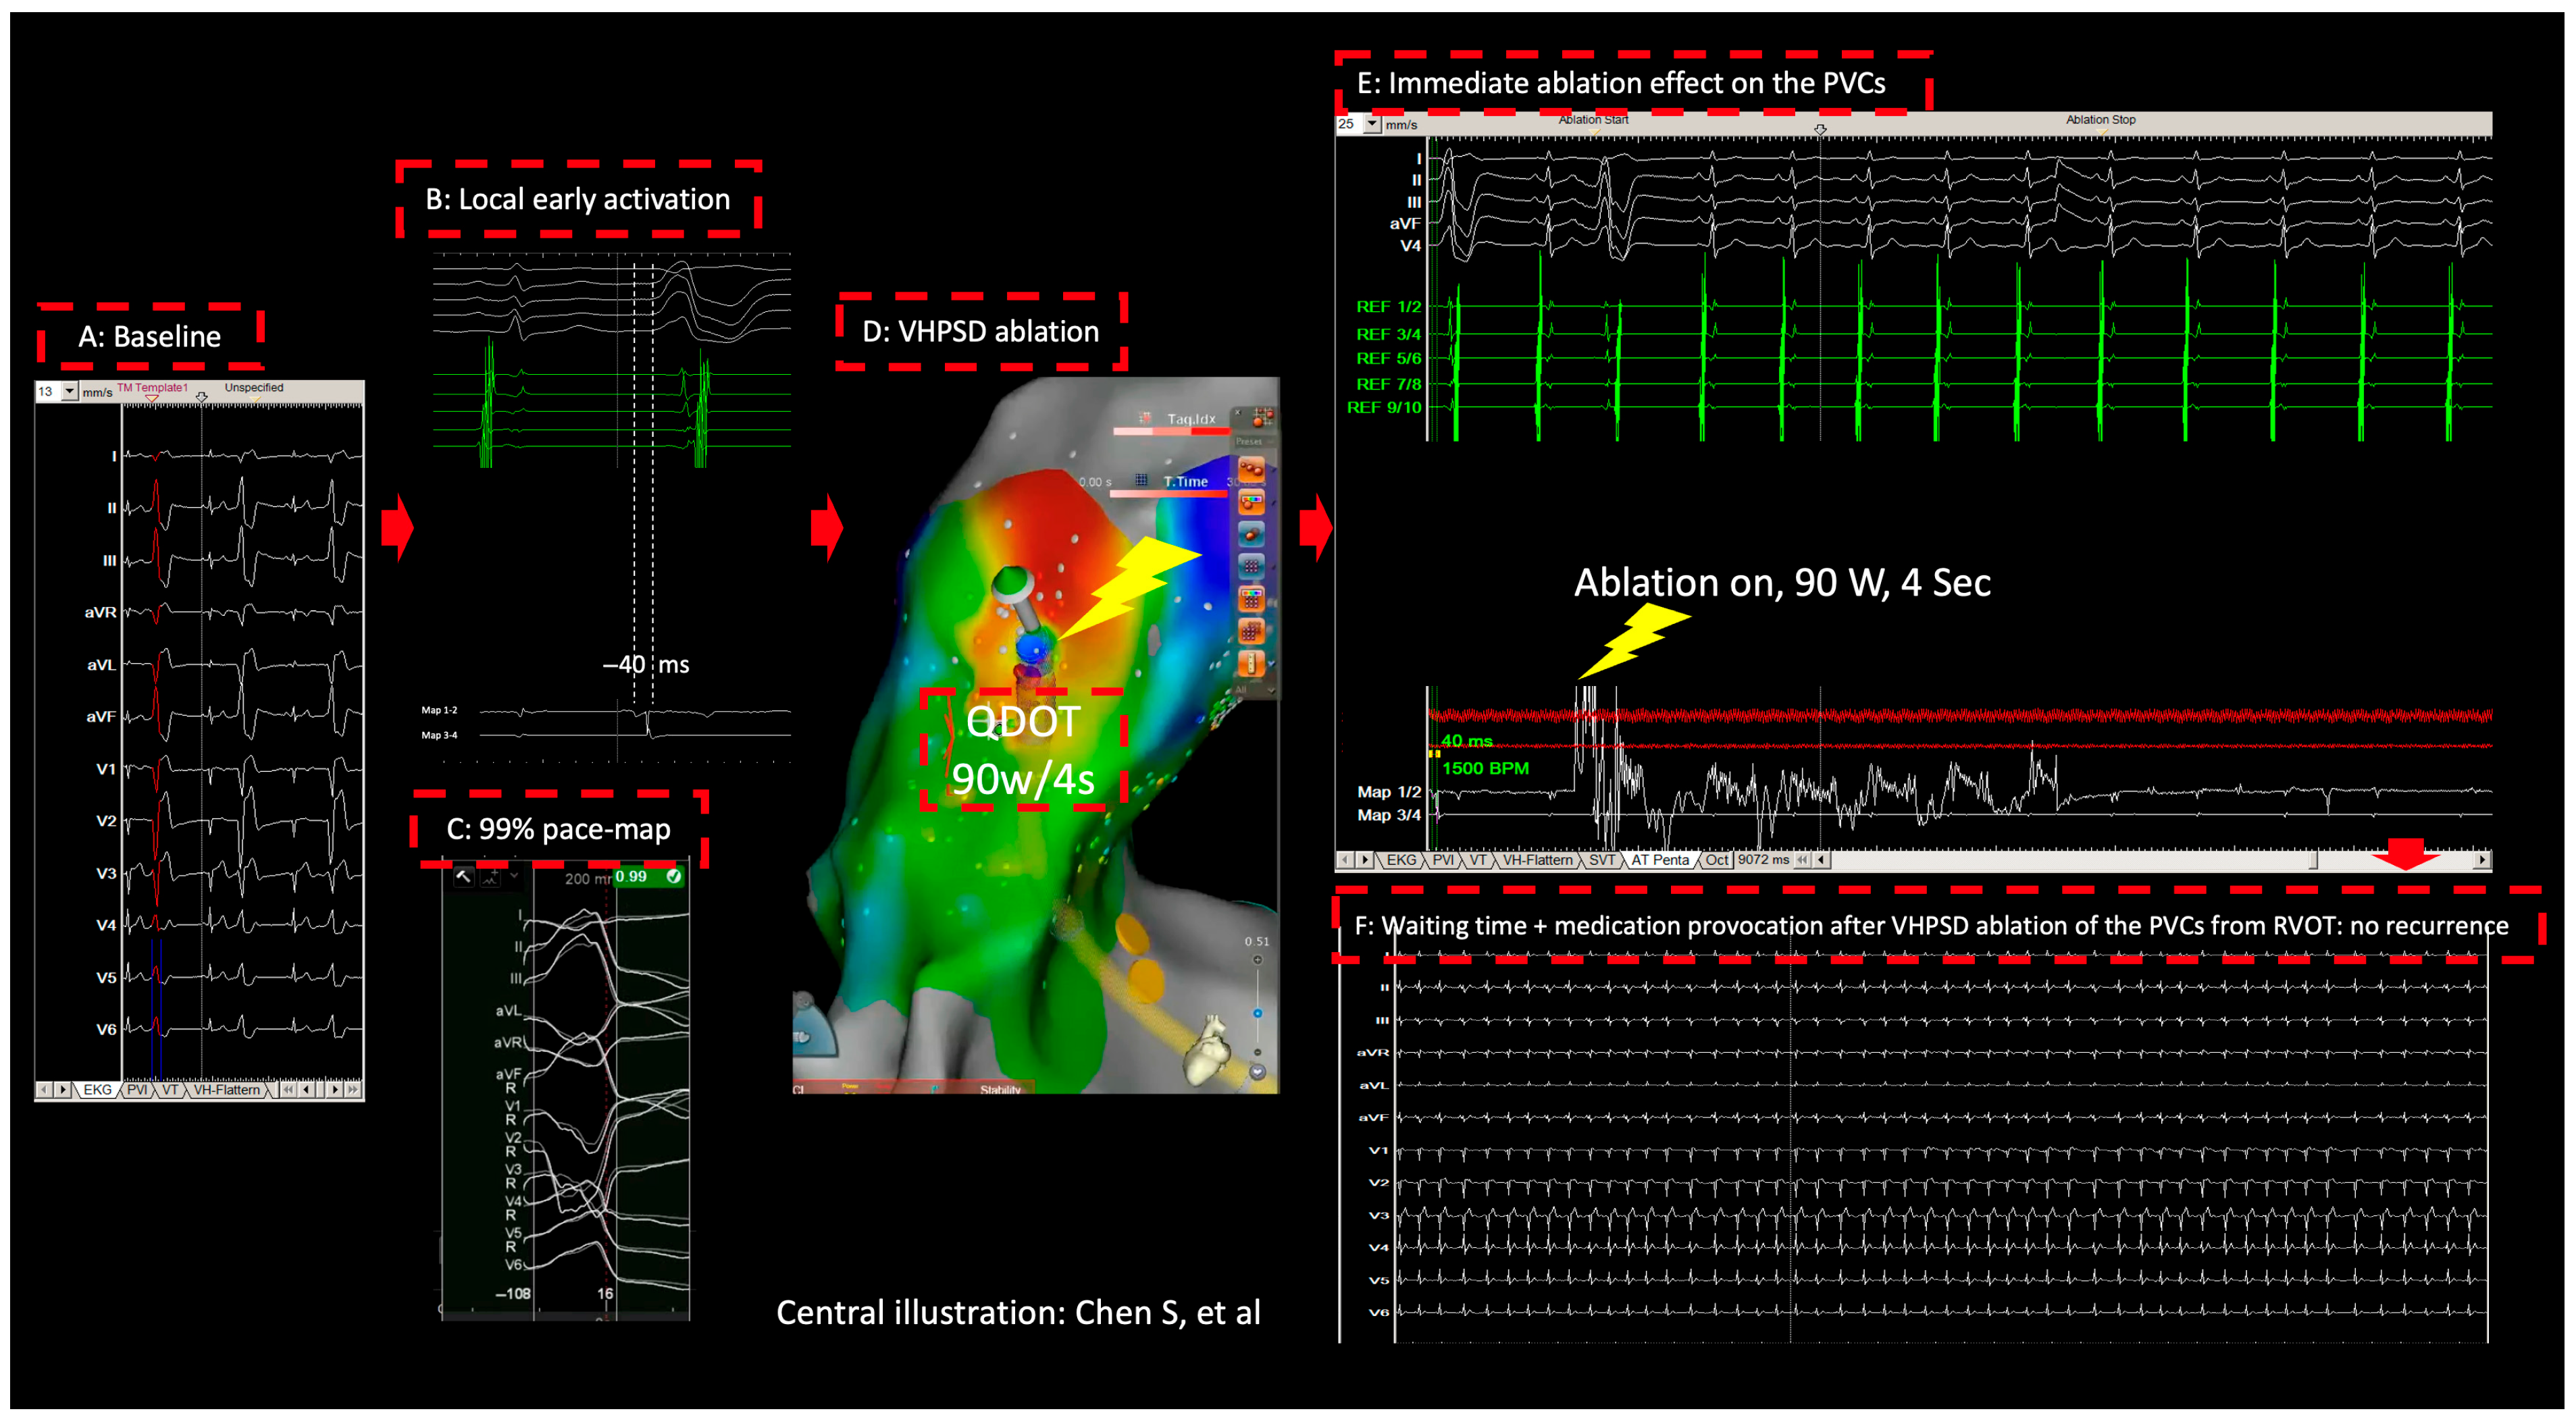

2. Method and Results